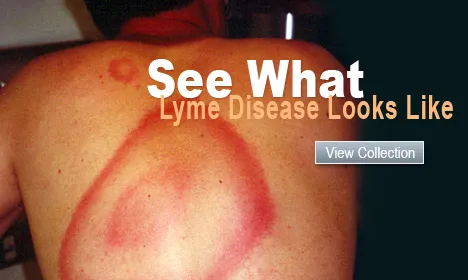

Picture of Lyme Disease

View a picture of Lyme disease which is transmitted through a bite from a specific type of tick carried by mice, deer, raccoons, opossums, skunks, squirrels and other animals. Learn about the signs and symptoms as well as what the disease looks like.

Lyme Disease

Lyme DiseaseLyme disease is transmitted by the bite of a tick infected with Borrelia burgdorferi. After a bite, an expanding bulls-eye rash develops. Facts on chronic Lyme disease tests, symptoms, treatment, diagnosis, stages, and prevention.

Picture of Lyme Disease

Picture of Lyme DiseaseLyme disease is transmitted through a bite from a specific type of tick. See a picture of Lyme Disease and learn more about the health topic.

What Is Lyme Disease? Symptoms, Rash, Treatments

What Is Lyme Disease? Symptoms, Rash, TreatmentsWhat is Lyme disease? Learn about symptoms and testing for Lyme disease, whether it is curable, and signs of Lyme disease caused by tick bites. See pictures of Lyme disease rashes and ticks that carry Lyme disease.